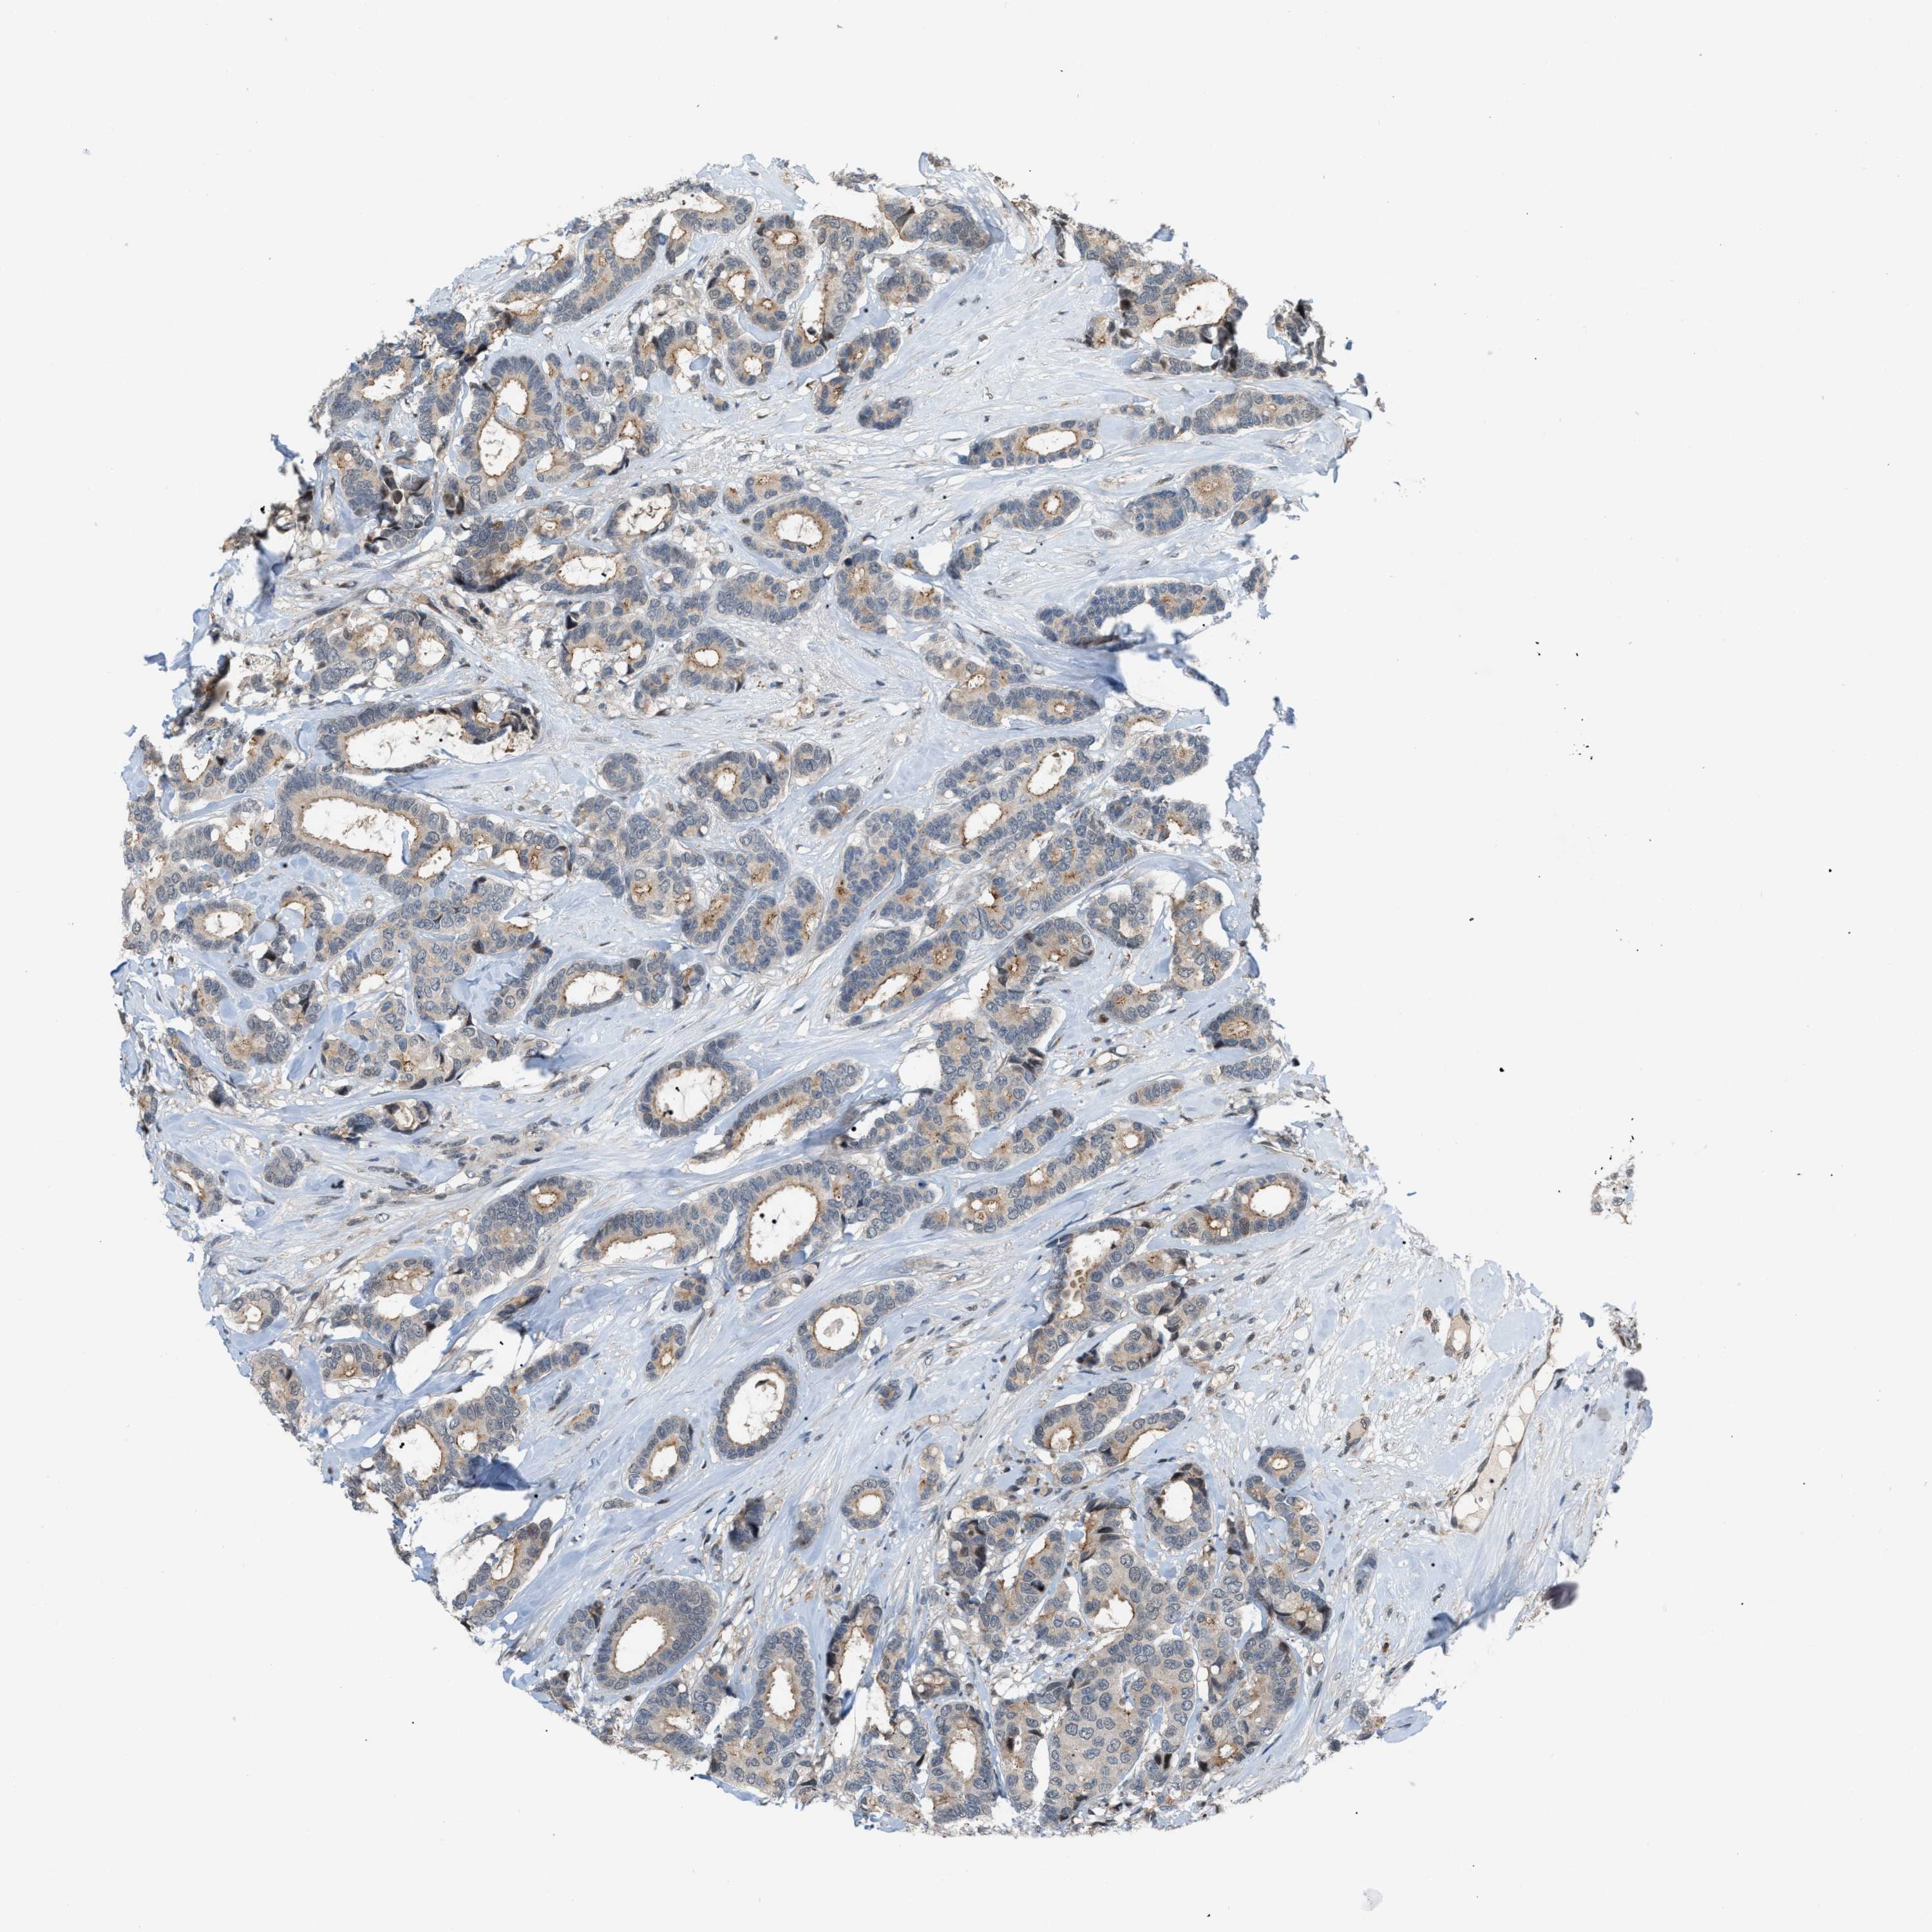

CANCER BREAST CANCER Show tissue menu

BRCA TCGA BRCA VALIDATION PROTEIN EXPRESSION

ANTIBODIES

AND

VALIDATION